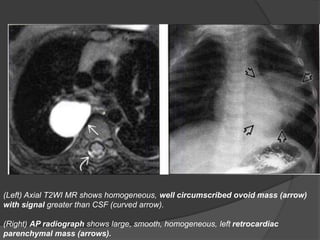

(Left) Axial T2WI MR shows homogeneous, well circumscribed ovoid mass (arrow)

with signal greater than CSF (curved arrow).

(Right) AP radiograph shows large, smooth, homogeneous, left retrocardiac

parenchymal mass (arrows).

(Left) Axial T2WIMR shows homogeneous, well circumscribed ovoid mass (arrow) with signal greater than CSF (curved arrow). (Right) AP radiograph shows large, smooth, homogeneous, left retrocardiac parenchymal mass (arrows).